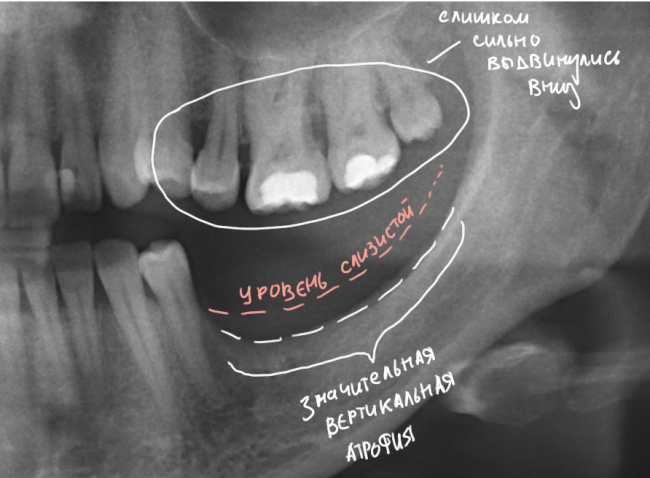

Итак, вот изначальная ситуация:

Я понимаю, что данных на части панорамного снимка очень мало для правильной интерпретации клинической ситуации, но, с другой стороны, это позволит не перегрузить Вас информацией.

Дано:

- боковой сегмент, отсутствуют три зуба: 35, 36, 37. Эти зубы удалены достаточно давно, развилась сильная атрофия костной ткани.

- верхние зубы, не имея антагонистов, выдвинулись вниз (зубоальвеолярное удлинение, т. н. «симптом Попова-Годона»).

Анализируем возможные проблемы:

Их несколько, они обозначены на снимке.

- Значительная атрофия костной ткани, особенно по высоте. Решается: остеопластической операцией.

- Дефицит слизистой оболочки почти всегда сопровождает атрофию кости. Следовательно, после имплантации (либо до нее) нам потребуется пластика десны. Я предпочитаю это делать на этапе установки формирователей десны.

- Зубоальвеолярное удлинение в области зубов-антагонистов. Решается: ортодонтическим лечением.